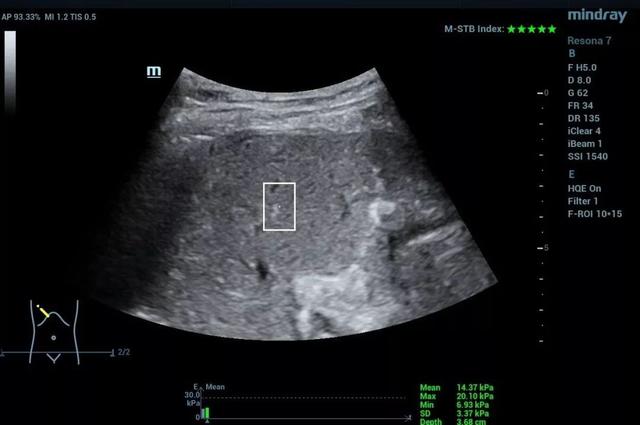

2. 点式剪切波弹性成像(pSWE/STQ)

当外力为声辐射力时,也就是说用探头来发射激励,在一定深度的组织聚焦,产生剪切波并被检测。这样克服了只有一维图像的困扰,对于肝脏也不怕肝前腹水的影响了。可是,能够被检测的范围比较小。

肝脏STQ图